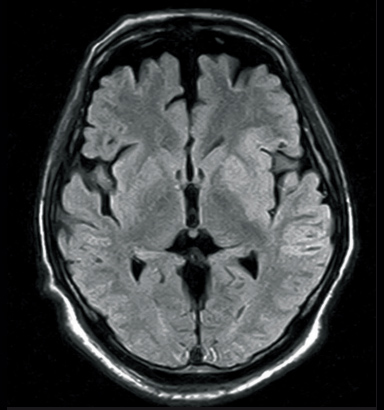

FLAIR